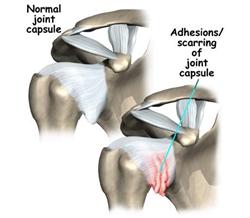

Some middle-aged or elderly people often feel pain in their shoulders and cannot raise their arms, even though they have never had any major injury. The symptom may become worse and the pain can radiate to the neck, forearms and hands. In more serious cases, great pain will be felt even when touched gently, and the pain may cause the sufferer to become awoken. Their shoulder movements are clearly limited, being unable to put on their shirt, fasten their belt or comb their hair. This is known as frozen shoulder and is also known as adhesive capsulitis or shoulder contracture.

Some middle-aged or elderly people often feel pain in their shoulders and cannot raise their arms, even though they have never had any major injury. The symptom may become worse and the pain can radiate to the neck, forearms and hands. In more serious cases, great pain will be felt even when touched gently, and the pain may cause the sufferer to become awoken. Their shoulder movements are clearly limited, being unable to put on their shirt, fasten their belt or comb their hair. This is known as frozen shoulder and is also known as adhesive capsulitis or shoulder contracture.Frozen shoulder is a chronic inflammation of the soft tissues of the muscle, tendon, bursa and articular capsule, causing adhesion of the joints and limitation of shoulder movements. X-ray examinations may show a sign of calcification in the shoulders. The frozen shoulders may be related to degeneration of tissues of the elderly. They can also be caused by catching a cold, repetitive strain injuries, or lack of movement.

Using acupuncture and Chinese medicine to treat frozen shoulder may improve the blood circulation of the shoulders, loosen the adhesions and relieve spasms, resulting in diminishing inflammation and pain, restoring the normal function of the shoulders. The practitioners at our clinic are very passionate about helping frozen shoulder sufferers to regain normal health.